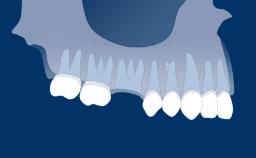

Introduction to Implant Dentistry

Pharmacology with Relevance to Dental Implant Therapy

- describe medications or conditions that might influence the healing process following implant surgery